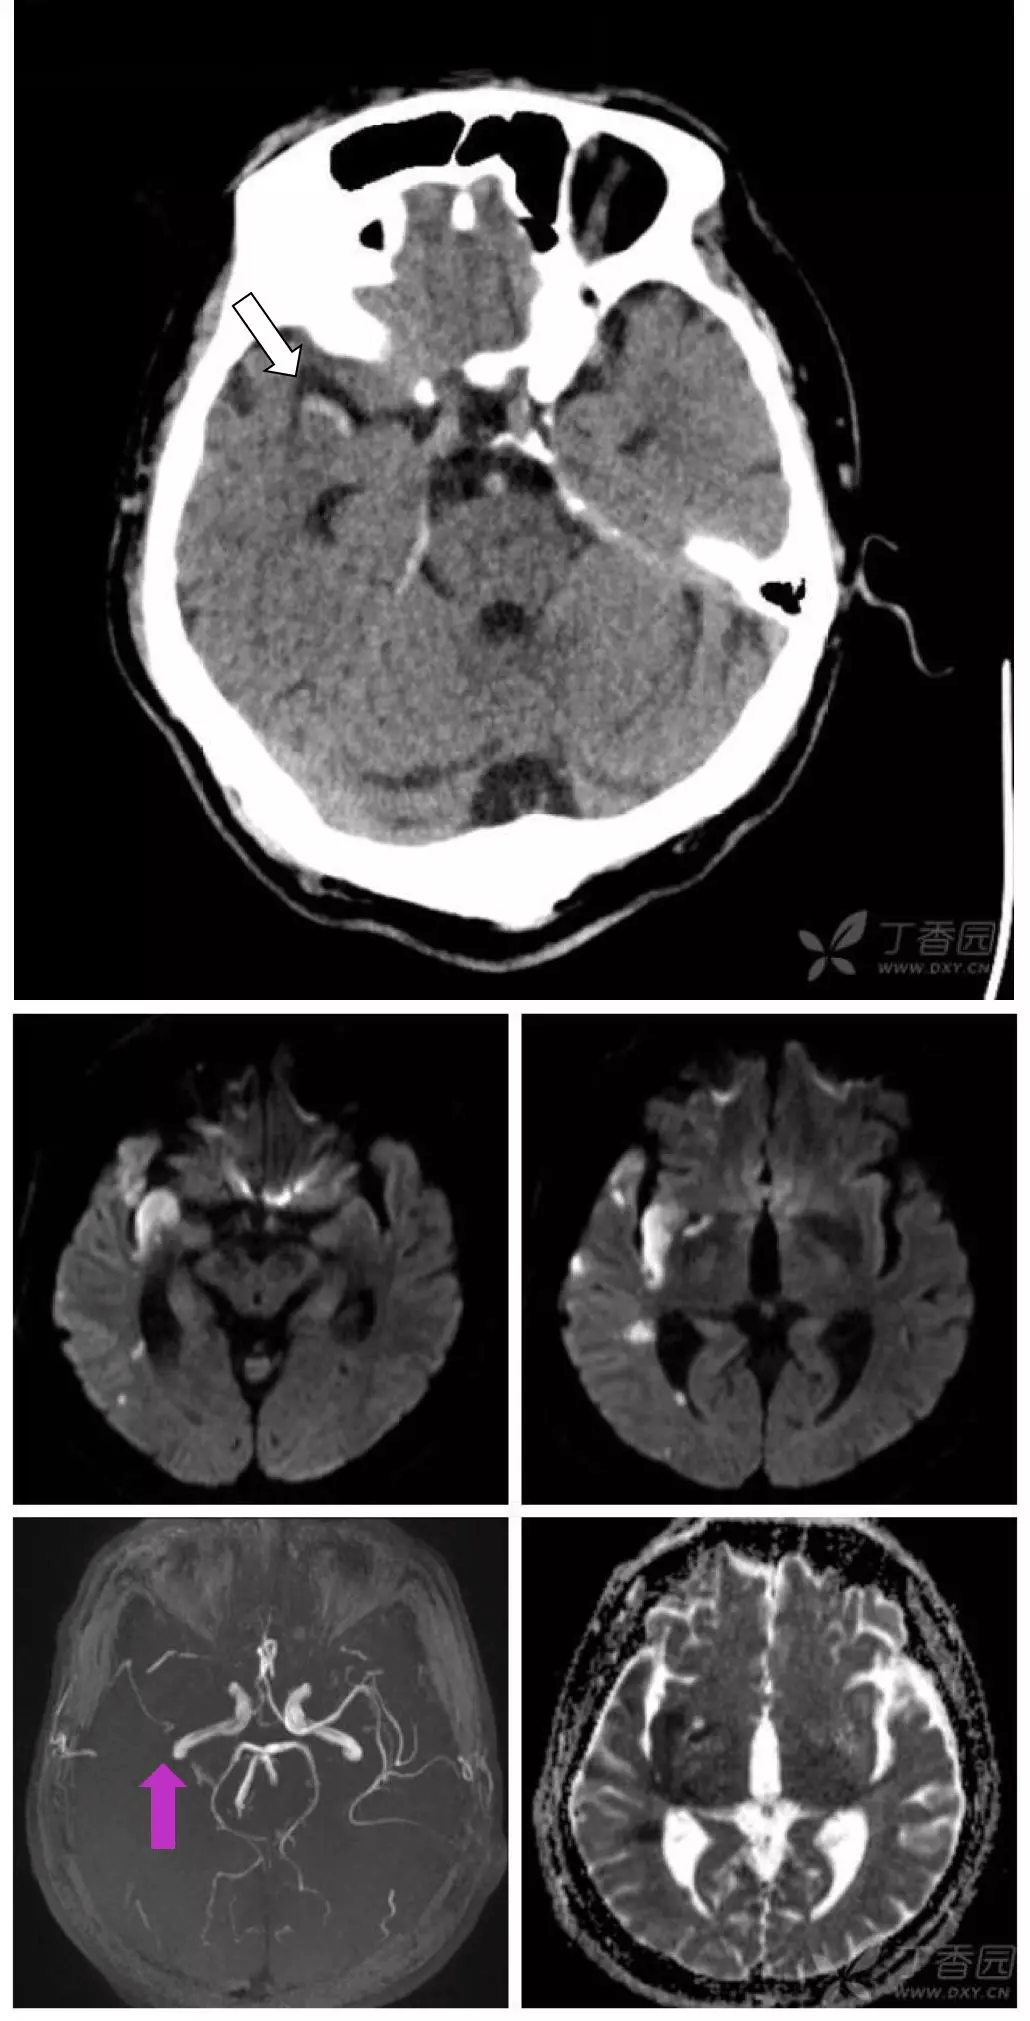

6 个病例学会「脑梗死」的 4 大 ct 征象

新生儿4天做ct和磁共振显示脑部有大片阴影,怎么办?

小脑出血穿刺治疗前后的ct图片

脑出血图片ct

脑梗图片ct